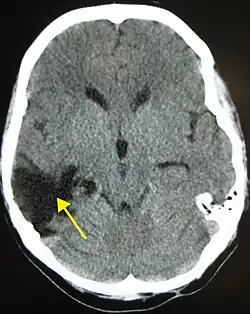

| A CT of the head years after a traumatic brain injury showing an empty space where the damage occurred, marked by the arrow | |

There are several imaging techniques that can aid in diagnosing and assessing the extent of brain damage, such as computed tomography (CT) scan, magnetic resonance imaging (MRI), diffusion tensor imaging (DTI) magnetic resonance spectroscopy (MRS), positron emission tomography (PET), and single-photon emission tomography (SPECT). CT scans and MRI are the two techniques widely used and are most effective. CT scans can show brain bleeds, fractures of the skull, fluid build up in the brain that will lead to increased cranial pressure.[37]